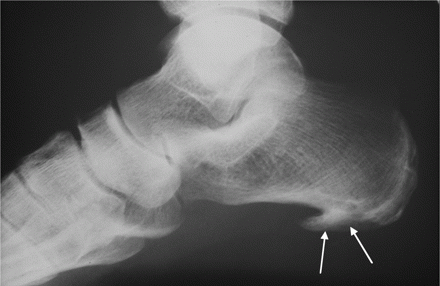

На рентгеновском снимке это новообразование выглядит как крючок или шпора, что и дало название заболеванию. В медицинской терминологии оно называется плантарный фасцит.

Для более точного определения проблемы рекомендуется обратиться к врачу. При осмотре воспаленного участка могут возникать болезненные ощущения, а для подтверждения диагноза назначаются дополнительные исследования. Современные методы диагностики, такие как рентген, МРТ и УЗИ, позволяют тщательно изучить состояние тканей. Завершив обследование, можно выявить патологию до того, как она перейдет в хроническую стадию.